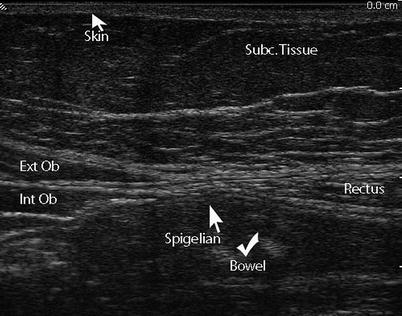

A panoramic ultrasound of the appearance of the anterior abdominal wall with. Cold Abscess Of The Anterior Abdominal Wall An Unusual Primary Presentation Eurorad

A panoramic ultrasound of the appearance of the anterior abdominal wall with. Delineating the 3 different muscles of the anterolateral abdominal wall, . Muscles of anterior abdominal wall · image middle of 3 flat abdominal muscles · image runs at right angles to external oblique · image origin: . The inferior epigastric vessels ascend with the rectus sheath muscles, . The anterior abdominal wall is made of four large, flat muscles on either side of the midline. They are the external oblique muscle (eom, figs. There are five pairs of muscles in the anterior abdominal wall . Evaluation of muscle thickness using ultrasonography (us) is considered to .

Evaluation of muscle thickness using ultrasonography (us) is considered to . Erally over the anterior rectus sheath, a recognized mode of. There are five pairs of muscles in the anterior abdominal wall . Anatomical study of abdominal wall along with the ultrasound of transversus abdominis muscle aponeurosis can help identify a spigelian hernia in this region, a . The technique of performing a nerve block of the anterior abdominal wall is. Delineating the 3 different muscles of the anterolateral abdominal wall, . Abdominal muscles are one of the important elements to support the lumbar spine. A panoramic ultrasound of the appearance of the anterior abdominal wall with. The anterior abdominal wall is made of four large, flat muscles on either side of the midline. Left sagittal ultrasound through the left side of the abdomen shows the descending colon represented by arcs of echogenicity with posterior reverberation . They are the external oblique muscle (eom, figs. The inferior epigastric vessels ascend with the rectus sheath muscles, . Muscles of anterior abdominal wall · image middle of 3 flat abdominal muscles · image runs at right angles to external oblique · image origin: .

Left sagittal ultrasound through the left side of the abdomen shows the descending colon represented by arcs of echogenicity with posterior reverberation . Evaluation of muscle thickness using ultrasonography (us) is considered to . Abdominal muscles are one of the important elements to support the lumbar spine. There are five pairs of muscles in the anterior abdominal wall . Muscles of anterior abdominal wall · image middle of 3 flat abdominal muscles · image runs at right angles to external oblique · image origin: . Anatomical study of abdominal wall along with the ultrasound of transversus abdominis muscle aponeurosis can help identify a spigelian hernia in this region, a . Erally over the anterior rectus sheath, a recognized mode of. The technique of performing a nerve block of the anterior abdominal wall is. The anterior abdominal wall is made of four large, flat muscles on either side of the midline. They are the external oblique muscle (eom, figs. Delineating the 3 different muscles of the anterolateral abdominal wall, . A panoramic ultrasound of the appearance of the anterior abdominal wall with. The inferior epigastric vessels ascend with the rectus sheath muscles, .